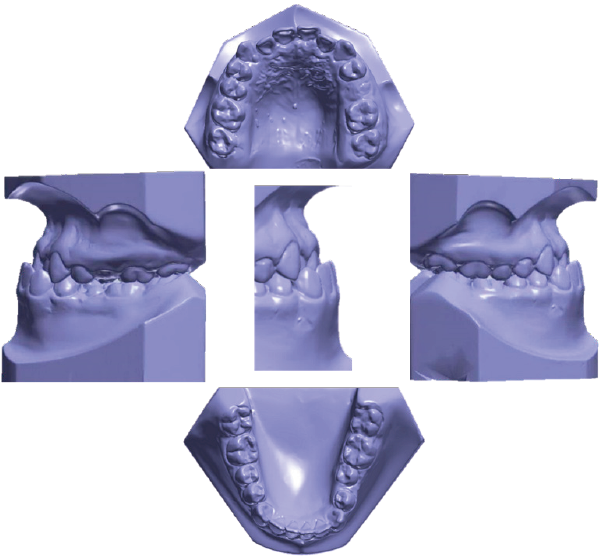

Paciente masculino de 12 años que asistió a la clínica de ortodoncia de la DEPeI de la Facultad de Odontología UNAM, donde tenemos sus registros fotográficos (Figura 1), radiológicos (Figura 2) y digitales (Figura 3). El diagnóstico facial consistió en un perfil cóncavo, proquelia inferior y biotipo euriprosopo. Cefalométricamente el paciente presentó Clase III esquelética combinada por retrusión y prognatismo, con un tipo de crecimiento horizontal (Figura 2.B). Dentalmente, clase III molar y canina bilateral y mordida cruzada anterior.